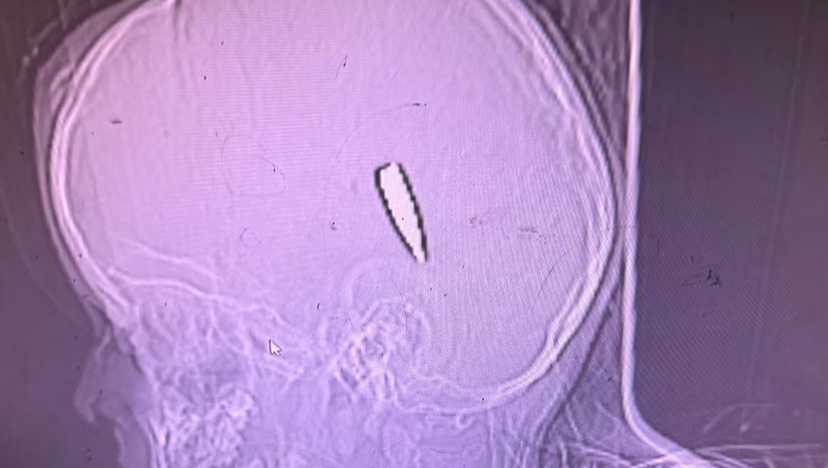

Ett av barnen som träffats i skallen, på en av bilderna som Mimi Syed tog under arbetet i Gaza.